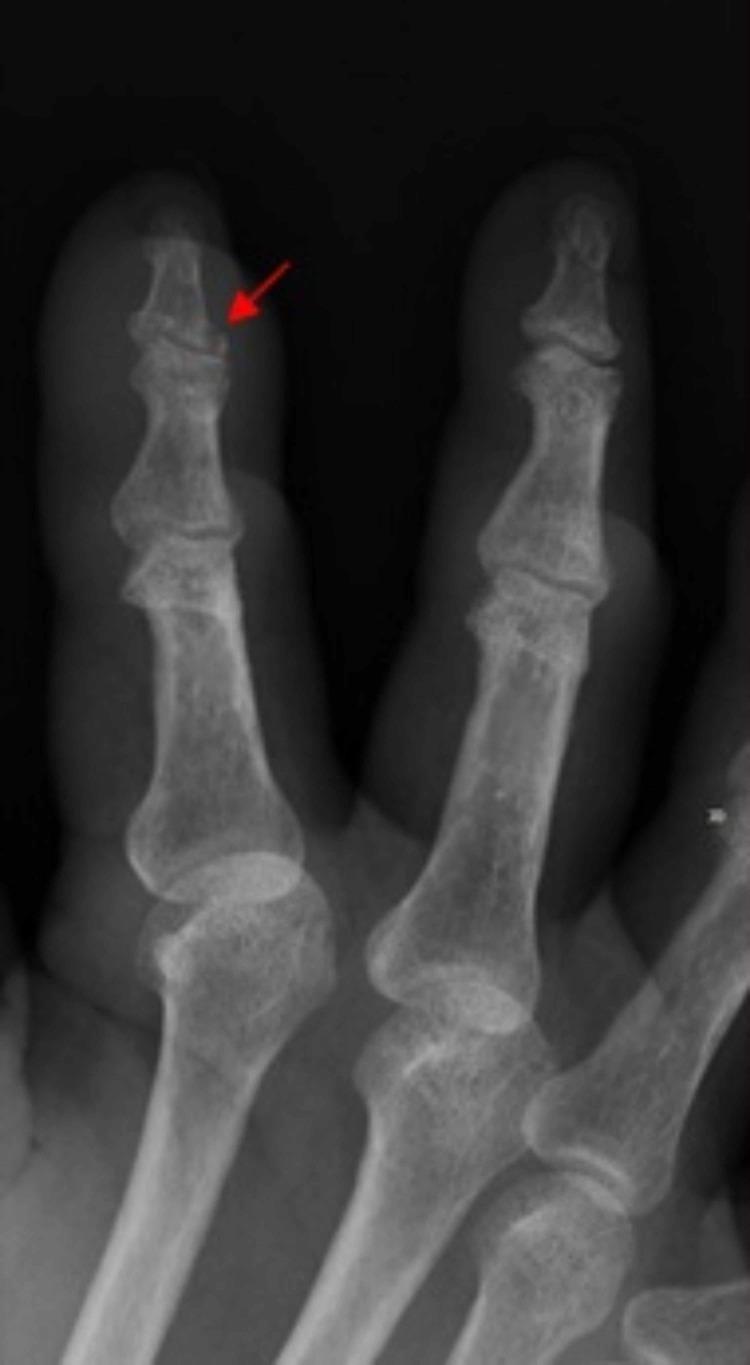

Unusual Subacute Interphalangeal Tophaceous Gouty Arthritis.

Gout is an arthritic syndrome that causes extensive joint damage and discomfort. It is due to an elevated uric acid level in the blood which deposits in the joints. This causes an inflammatory response and joint damage. Gout typically presents as an acute monoarticular attack, resulting in hot, erythematous, swollen, and exquisitely tender joint. Tophaceous gout, which is commonly a later complication of long-standing gout, can rarely be the presenting manifestation of gout. Tophaceous gout is considered a late complication of chronic gout. As early recognition of gout can lead to prompt initiation of treatment and improvement in clinical status, a patient with an alcohol use history who presents with polyarticular swelling and tenderness should raise the suspicion of a tophaceous gout exacerbation even if the patient does not have a documented history of gout.